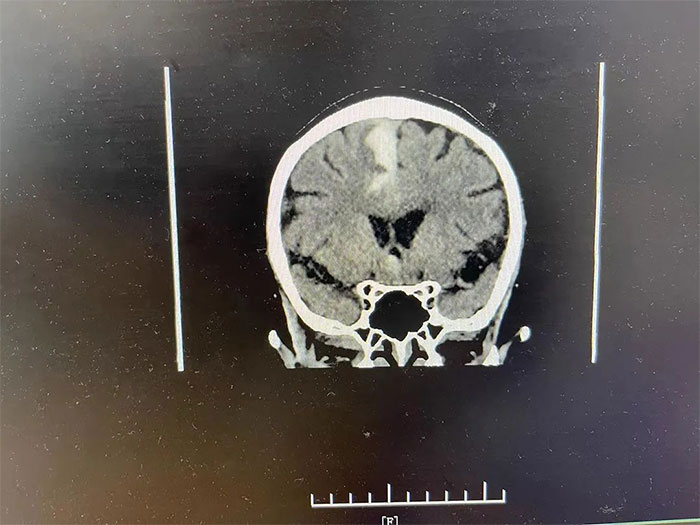

▲ 入院检查颅内仍有出血活动

更令人不安的是,CT检查显示,吴阿姨右侧大脑顶叶出血灶较前变化不明显,提示仍有出血活动,若不及时进行干预,随时都有“决堤”的可能,不仅影响神经功能恢复,病情还可能因之进一步恶化,甚至危及生命。